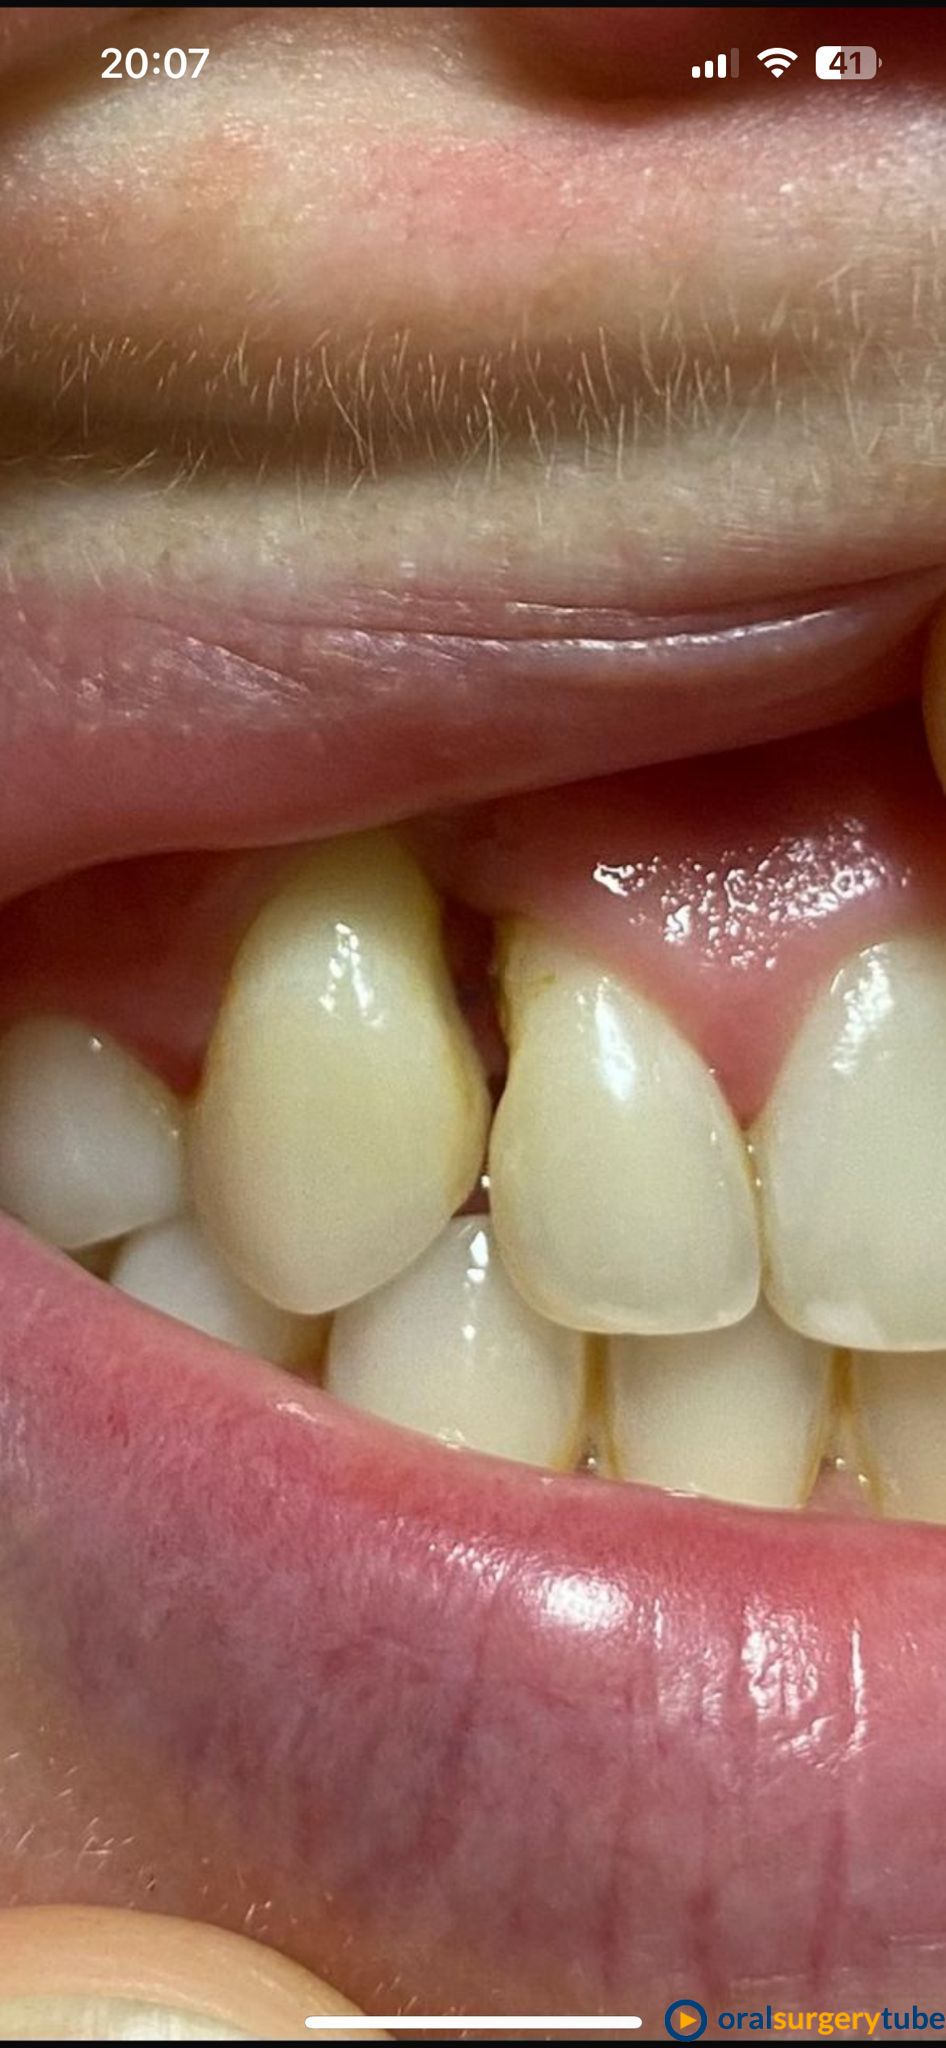

Seguimiento de caso de defecto vertical entre dos dientes (12 y 13) tras cirugía ortognática.

Paciente de mediada edad que es remitida para intentar mejorar el estado periodontal de los dientes 12 y 13 tras cirugía ortognática. A la paciente le habían realizado previamente varios injertos de tejido conectivo y empleo de Emdogain® sin éxito. Se plantea hacer técnica de Wall technique de Zucchelli modificada para simultanear técnicas de regeneración ósea guiada.

Bueno, me hubiera encantado poder cubrir toda la recesión, pero creo que hemos llegado al máximo que se podía.